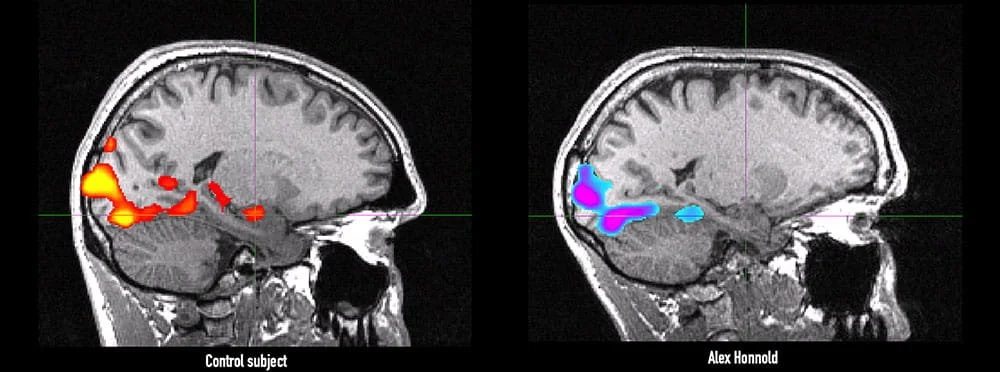

Seconds later, I found an article describing how neuroscientists had studied Alex’s brain using fMRI scans. His amygdala was not smaller than normal. It was the same size as everyone else’s. What was different was how it responded. His amygdala simply did not fire as quickly or as intensely when exposed to fear inducing stimuli.

In short, his brain registers threat differently than most.

Imagine having just a bit less fear in the moments that matter most. The biggest games. The highest pressure situations in your craft. To a degree, that is the world Alex Honnold experiences.